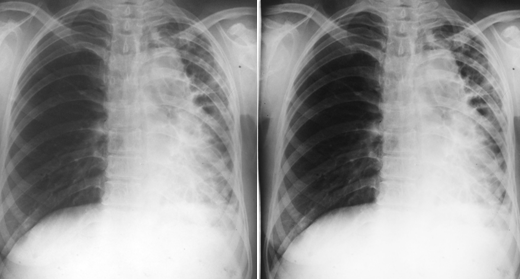

两肺支气管肺炎

图片

胸部正位片示:两肺多发不规则的小片状或斑片状边缘模糊的致密阴影,阴影密度不均,中间密度高,边缘淡,局部融合呈片状分布

两下肺支气管肺炎

胸部正位片示:两下肺可见不规则的小片状或斑片状边缘模糊的致密阴影,阴影密度不均